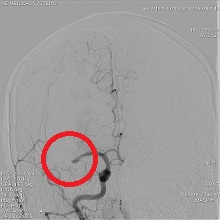

![]() 中大脳動脈閉塞

血栓除去術後(血流再開後)

急性の心筋梗塞・くも膜下出血・脳梗塞・動脈出血などに対応するアンギオ装置です。

24時間いつでも対応しております。